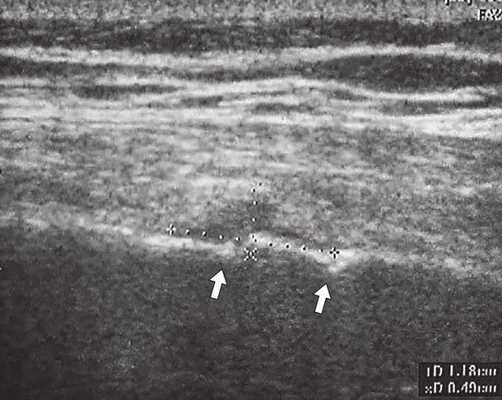

Исследование проводилось на аппаратах SonoAce-8000, SonoAce-X8 и Accuvix-V10 (компании Medison) линейными датчиками 5-9 и 5-12 МГц в В-режиме в положении пациента стоя, без специальной подготовки. Обследование начиналось с осмотра болевой точки, на которую указывал пациент, что является безусловным достоинством метода, обеспечивая точность и короткое время исследования. Во всех случаях были выявлены переломы VII, VIII или IX ребер грудной клетки с обеих сторон по передней, средней и задней подмышечной линиям. У одного из пациентов был выявлен перелом двух ребер (рис. 1, 2). Все переломы были неполные и без смещения. В пяти случаях наблюдался перелом с острым концом костного отломка (рис. 2-6), в одном - у пациента с переломом двух ребер - двойной "окончатый" перелом (см. рис. 1). В трех случаях в месте переломов наблюдалось местное кровоизлияние в мягкие ткани (см. рис. 1, 2, 4), которое визуализировалось в виде гипоэхогенной зоны небольших размеров.

Рис. 1. Двойной "окончатый" перелом VII ребра правой половины грудной клетки (указан стрелками).